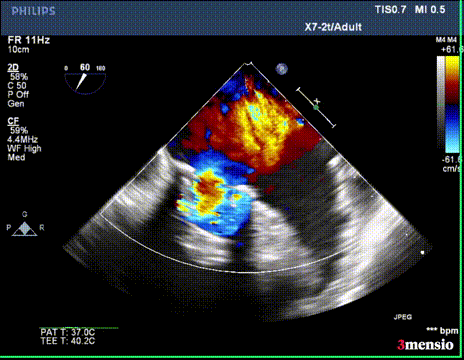

超声显示二尖瓣大量反流

切割前彩超